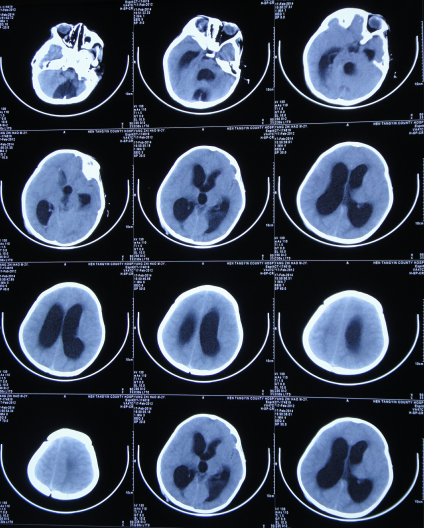

脑水肿脑积水的分类及影像表现一文归纳